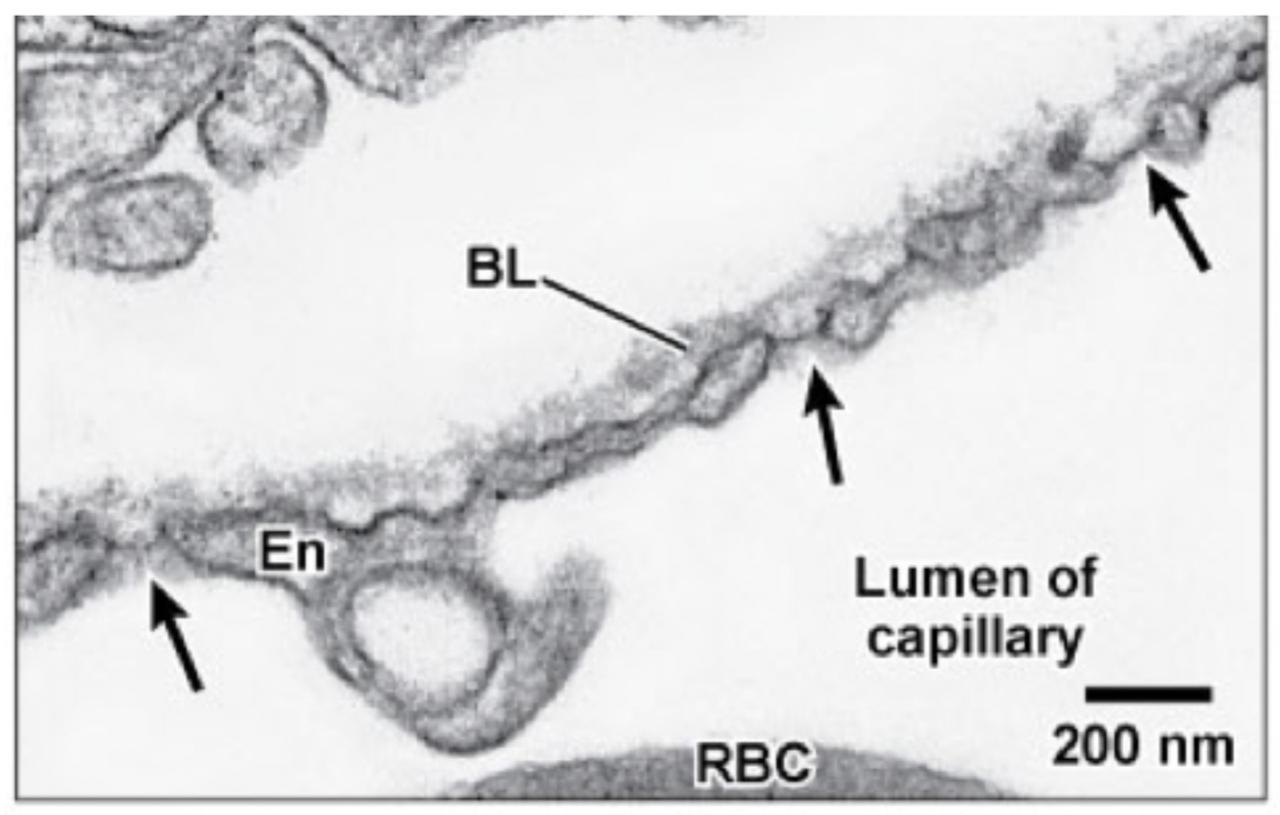

Fig 3.41: Algemene opbouw van een capillair

endotheel

lamina basalis grondsubstantie + reticulaire vezels -

pinocytotische vesikels

RBC (7-9 um, 2um doorsnede) plasma tight junctions (paars) -